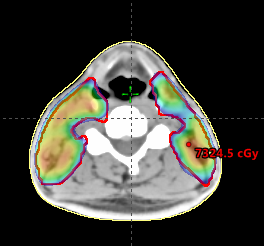

Li Kai Leung, Alex

Score: 99.0/ 100

Hospital: St. Teresa’s Hospital

Technique: VMAT

Rank: Fourth Top (Eclipse)

Job Title: Lead, Radiation Therapis